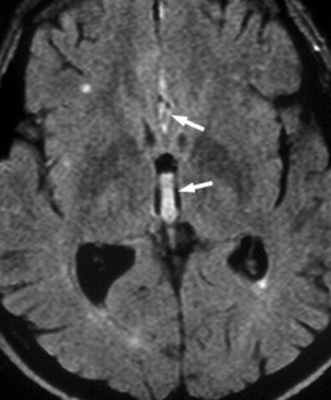

Диагноз спонтанной спинальной эпидуральной гематомы обычно верифицируется с помощью МРТ или компьютерной томографии в сочетании с миелографией. Спинальная ангиография в настоящее время редко используется для таких ургентных случаев, как острая спинальная эпидуральная гематома. Магнитно-резонансная томография (МРТ) является основным методом в диагностике СЭГ. Типичная МР-картина СЭГ заключается в визуализации экстрадурального объемного образования двояковыпуклой формы с четко определенными границами, сужающихся кверху и книзу. В первые 24 часа СЭГ равномерно изоинтенсивна на Т1 взвешенных изображениях, а на Т2 ВИ как правило гиперинтенсивна, но в некоторых случаях может иметь неоднородный сигнал. По истечению 48 часов, в подострой стадии, гематома, как правило, дает гетерогенный гиперинтенсивный сигнал как на Т1 ВИ, так и на Т2 ВИ. Усиление неоднородности сигнала происходит в результате образования дезокси-гемоглобина.

МРТ головного мозга. Аксиальная МРТ типа FLAIR. Аневризма и САК, внутрижелудочковое кровоизлияние.